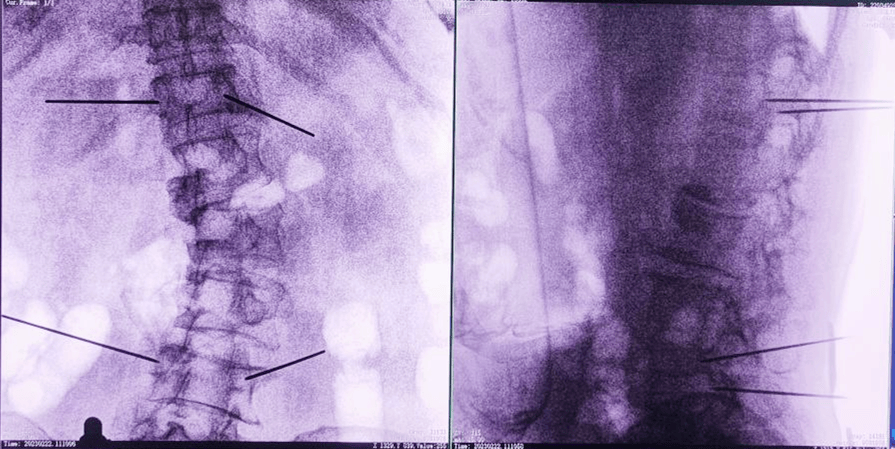

骨科导航机器人术中图像

平板三维C形臂采集图像

术中,手术团队先对患者进行三维影像扫描,将图像同步传输至机器人成像系统后,利用骨科导航机器人系统做好手术规划,随后利用其机械臂,将手术工具精确定位到“目的地”,铺好“通道”,这就很好的解决了医生“盲穿”的问题。